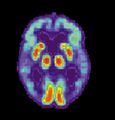

PET scan of brain with AD - Image courtesy of US National Institute on Aging Alzheimer's Disease Education and Referral Center

Alzheimer's disease (AD) is a progressive, degenerative and fatal brain disease, in which cell to cell connections in the brain are lost. Alzheimer's disease is the most common form of dementia.[2] Globally approximately 1–5% of the population is affected by Alzheimer's disease.[3] Women are disproportionately affected by Alzheimer's disease. The evidence suggests that women with AD display more severe cognitive impairment relative to age-matched males with AD, as well as a more rapid rate of cognitive decline.[4]